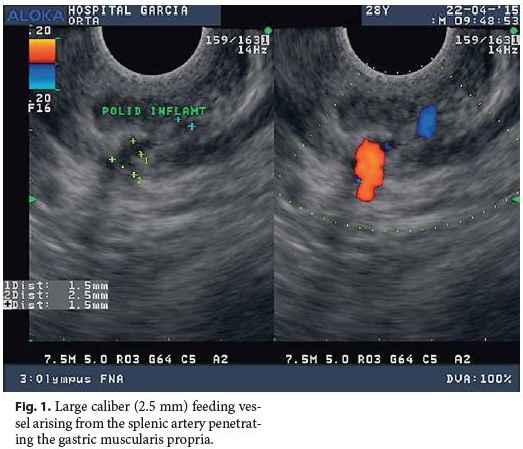

A 28-year-old man without any remarkable past medical history presented with hematemesis and hemodynamic instability. There was no significant past medical history. He denied any medication intake, namely nonsteroidal anti-inflammatory drugs, alcohol abuse, or smoking habits. Upper gastrointestinal endoscopy (UGE) revealed fresh blood and a giant clot covering the gastric body and fundus. Repeated UGE showed no mucosal defect. Radial endoscopic ultrasound (EUS) was performed, indicating a submucosal vessel arising in the greater curvature of the proximal gastric body which identified a Dieulafoys lesion as the possible source of bleeding. Considering clinical stability, EUS-guided therapy with linear scope was planned for the next morning when the scope was available, but rebleeding occurred. UGE was performed with a therapeutic scope, as the site of bleeding was already identified and active bleeding was expected. Thus, the advantages of a dual channel scope, which is more easily maneuvered, would outweigh the advantagesof using the echoendoscope, which has the main benefit when the Dieulafoys lesion cannot be identified on UGE because it is no longer bleeding. UGE revealed an adherent clot in the suspected Dieulafoys lesion location previously described on EUS. After the first clip deployment, massive bleeding occurred. Hemostasis was achieved after adrenalin and polidocanol injection and clipping. EUS was performed to confirm vessel obliteration but still identified a large caliber (2.5 mm) feeding vessel arising from the splenic artery penetrating the gastric muscularis propria (Fig. 1). Selective splenic artery angiogram as determined by EUS was performed, revealing a short gastric artery ectasia and hypervascularization (Fig. 2, large arrow) ending in the previously endoscopically placed clips (Fig. 2, small arrow). Superselective transcatheter arterial embolization (TAE) was performed, and the patient presented no further episodes of gastrointestinal bleeding at the 1-year follow-up.